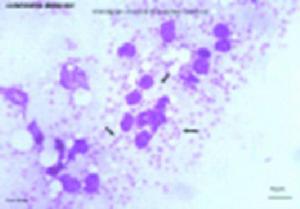

(3)血清特異性抗原抗體檢測陽性有助診斷、骨髓、淋巴結或脾、肝組織穿針塗片,找到利杜體或穿刺物培養查見前鞭毛體可確診。